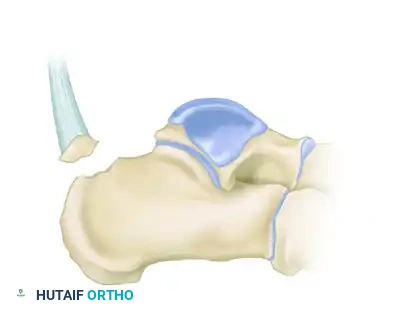

Understanding the morphology of the avulsion is critical for selecting the appropriate fixation strategy. These fractures are generally classified into three distinct types:

Type I: Sleeve Fracture

A thin sliver of cortical bone is avulsed from the posterior tuberosity, often involving the direct insertion of the Achilles tendon.

Type II: Beak Fracture

An oblique fracture exiting dorsally, creating a distinct "beak" fragment. This fragment is highly prone to proximal displacement due to the Achilles tendon.

Type III: Infrabursal Fracture

An avulsion fracture occurring lower on the tuberosity, typically sparing the primary Achilles insertion but involving the retrocalcaneal bursa region.

Soft Tissue Compromise: A Surgical Emergency

Displaced calcaneal avulsion fractures, particularly Type II beak fractures, represent a true orthopedic emergency. The proximally displaced fragment places immense pressure on the posterior skin of the heel. If not reduced expediently, the skin will blanch, blister, and rapidly progress to full-thickness necrosis.

Surgical Warning: A displaced calcaneal tuberosity fracture with skin blanching must be reduced immediately. Delaying surgery will result in catastrophic soft tissue loss over the Achilles tendon, necessitating complex flap coverage and drastically increasing the risk of deep infection.

Below is an example of a severe calcaneal avulsion with a large fragment threatening the posterior envelope: